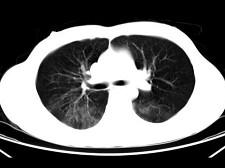

男,35岁,被车撞伤后1小时,结合影像图像选择其最可能的诊断为 ( )A、肺挫伤B、支气管扩张C、肺结核D、间质性肺炎E、肺炎

问题 男,35岁,被车撞伤后1小时,结合影像图像选择其最可能的诊断为 ( )

选项 A、肺挫伤 B、支气管扩张 C、肺结核 D、间质性肺炎 E、肺炎

答案 A